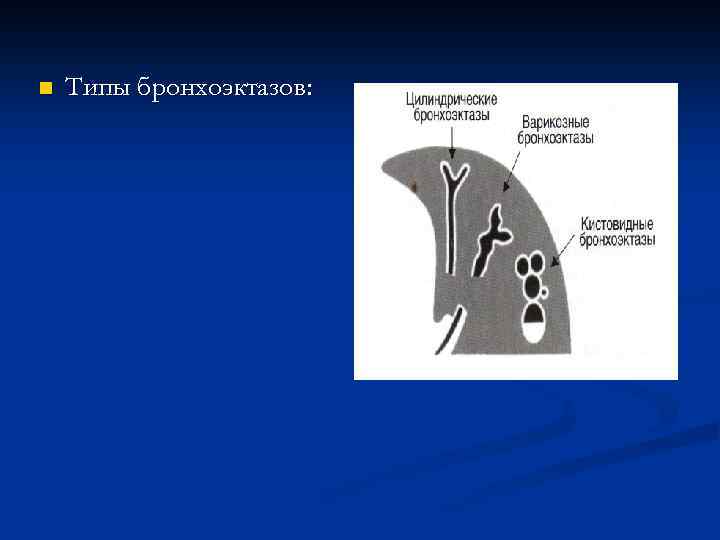

n Типы бронхоэктазов: